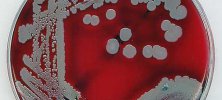

Nowy sposób na zabijanie MRSA tlenem

21 sierpnia 2018, 13:17Gronkowiec złocisty oporny na metycylinę (MRSA) to jedno z największych zagrożeń w szpitalach. Łatwo się rozprzestrzenia i jest trudny w leczeniu, powodując zakażenia szpitalne.